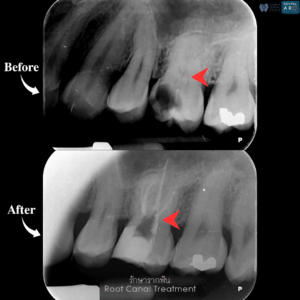

รักษารากฟัน

คือ การรักษาฟันที่เกิดการอักเสบและติดเชื้อภายในโพรงประสาทฟัน และเนื้อเยื่อรอบปลายรากฟัน อันมีสาเหตุมาการอักเสบและติดเชื้อภายในรากฟัน โดยทันตแพทย์จะทำการทำความสะอาดและใส่ยาในคลองรากฟัน และทำการอุดรากฟันเป็นขั้นตอนสุดท้าย การรักษารากฟันจะช่วยเก็บรักษาฟันให้สามารถคงอยู่ในช่องปากต่อได้ โดยไม่ต้องถอนฟันและไม่ต้องใส่ฟันทดแทน